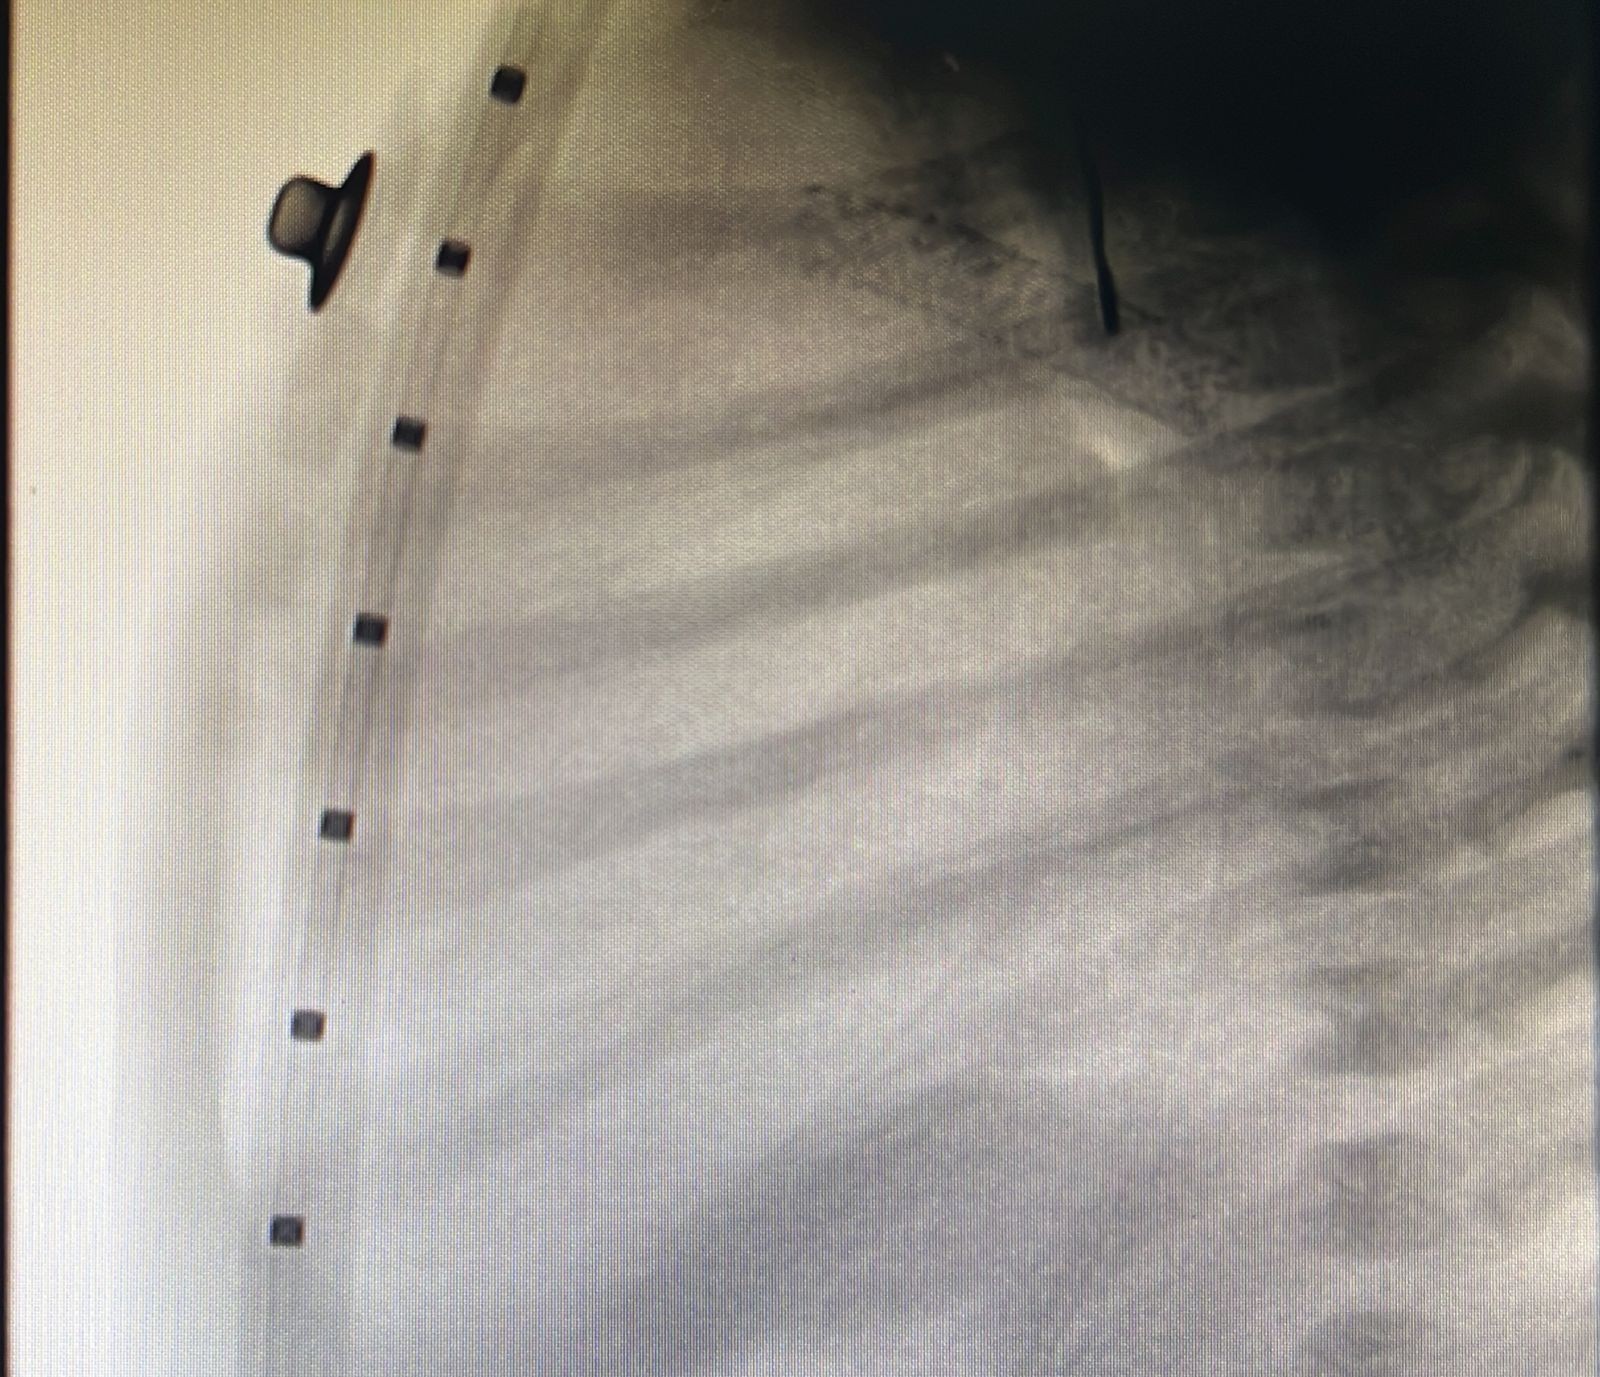

وأوضح تجمع القصيم الصحي أن الفحوصات والأشعة التي أجريت للرضيع الذي تم تحويله للمركز من خارج منطقة القصيم ويزن ثلاثة كيلوجرامات، أظهرت بوضوح أنه كان يعاني من انسداد كامل في صمام الشريان الرئوي؛ مما تسبب له بانقطاع تام للدورة الدموية لكامل الجسم.

وأشار التجمع إلى أنه تم خلال التدخل الطبي غير الجراحي تركيب دعامة للقناة الشريانية ما بين الشريان الأورطي والرئوي بهدف إيصال الدم للرئتين، إضافة إلى توسيع ثقب أذيني لاستفادة الجسم بخلط الدم المؤكسج وغير المؤكسج، وقد تكللت عملية القسطرة بالنجاح، وبعد الاطمئنان على وضعه الصحي غادر المركز برفقة ذويه وهو في حالة مستقرة ولله الحمد.